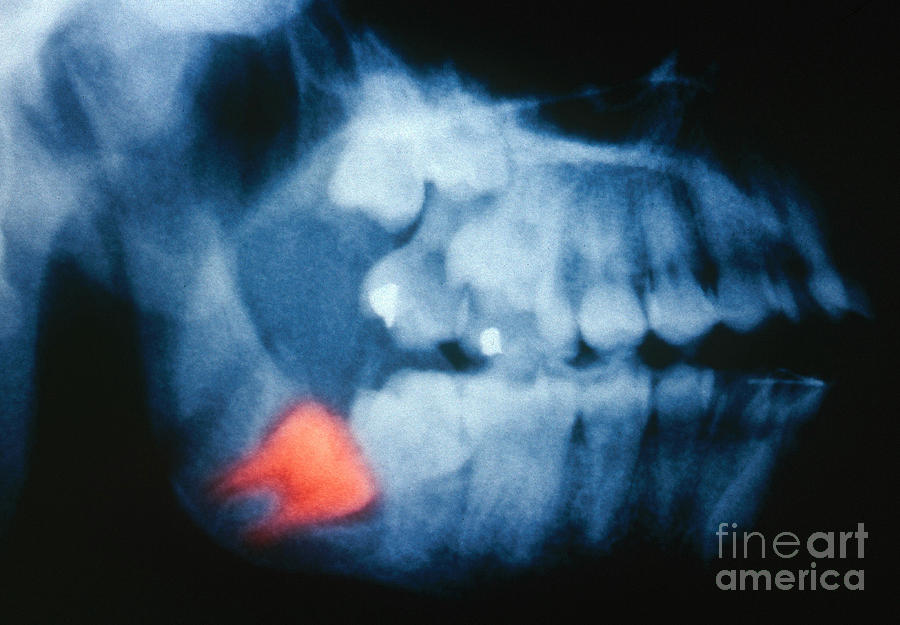

Coloured X-ray Of Impacted Wisdom Tooth And Brace - Stock Image - M782

www.sciencephoto.comtooth wisdom ray coloured brace impacted

www.sciencephoto.comtooth wisdom ray coloured brace impacted

www.dreamstime.comImpacted Wisdom Tooth, X-ray Photograph By Scott Camazine

www.dreamstime.comImpacted Wisdom Tooth, X-ray Photograph By Scott Camazine

pixels.comwisdom tooth impacted camazine scott 28th

Impacted Wisdom Tooth, Panoral X-ray - Stock Image - C015/2819

www.sciencephoto.comtooth impacted wisdom ray

www.sciencephoto.comtooth impacted wisdom ray

www.temeculafacialoralsurgery.comImpacted Wisdom Tooth, X-ray Photograph By Scott Camazine

www.temeculafacialoralsurgery.comImpacted Wisdom Tooth, X-ray Photograph By Scott Camazine

fineartamerica.comcamazine impacted

fineartamerica.comcamazine impacted